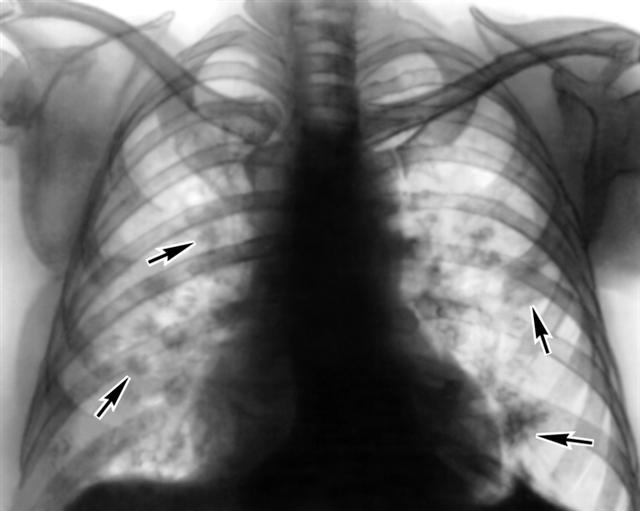

Рис. 1б). Рентгенограмма грудной клетки (прямая проекция) больного с эозинофильными летучими инфильтратами — множественные инфильтраты в правом и левом легких (указаны стрелками).